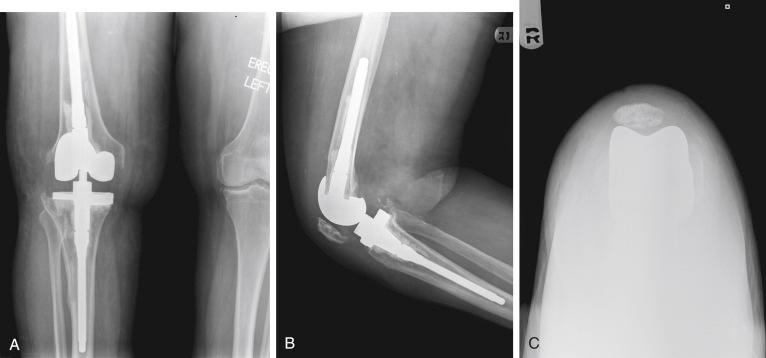

A 55-year-old woman presented to the office with persistent anterior knee pain and swelling after a revision total knee arthroplasty (TKA) performed 1 year earlier. She reported some subjective instability and difficulty descending stairs. She denied having any postoperative wound complications or constitutional symptoms, and the workup for infection included serologic and aspiration fluid analyses that were negative. Physical examination demonstrated a well-healed midline incision and a mild effusion without warmth. Standing alignment revealed a varus deformity at the knee, which was partially correctible. She had moderate peripatellar tenderness in response to palpation. Range of motion was preserved. The patella dislocated laterally during active and passive knee flexion. Initial radiographs demonstrated a cemented, stemmed revision total knee with a tibial component that was implanted in varus. Rotational malalignment was suggested by the asymmetry of the tibial keel on the anteroposterior view and the dislocated patella on the sunrise view ( Fig. 24.1 ).

FIGURE 24.1, Revision total knee arthroplasty was performed with a tibial component that was implanted in varus. Preoperatively, malrotation was suspected based on the rotational profile of the tibial keel seen on the anteroposterior radiograph ( A ) and the dislocated patella seen on the sunrise view ( B ). C, On the lateral radiograph, no gross errors in component position or sizing are noted.